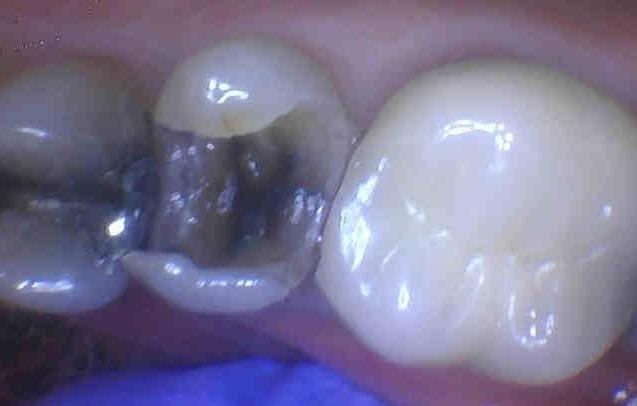

Cracked Silver Filling Removed and Replaced with Composite

This tooth had an old, average-size silver filling. However, the silver (amalgam) filling had several crack lines in it. When a silver filling has cracks in it like these, bacteria can get through the cracks and cause dental decay. The amalgam filling was removed which revealed a significant amount of decay. Fortunately, the decay did not go into the nerve of the tooth and it was restored with a large, bonded composite.